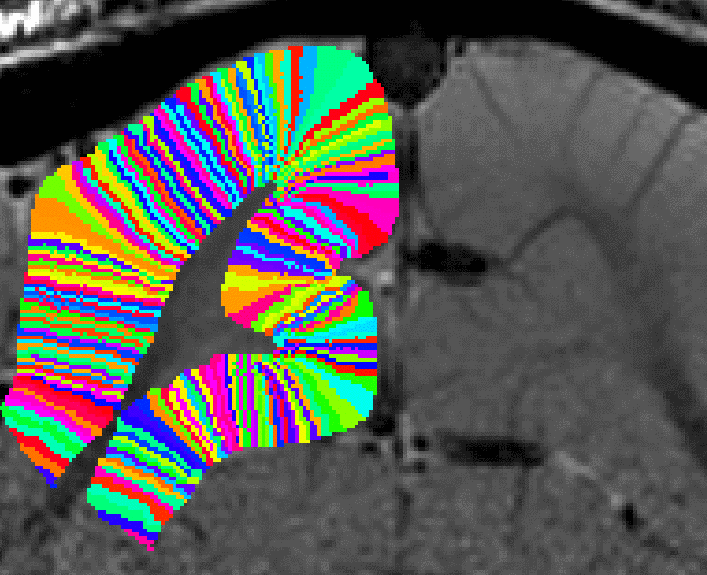

The result is a layer file layers.nii looking like this

Note on single slice data (e.g. for Shinho Cho ): when the “-threeD” flag is not set, the program LN_GROW_LAYERS estimates the layers on a slice-by-slice basis. This is done assuming that the slice direction is the third dimension in the nii header according to the default of x-y-z,as phase-read-slice. If your data are not stored like this, consider using the “-threeD” option in LN_GROW_LAYERS. Alternatively, the dimentsion can be exchanged with fslswapdim input x z y output.